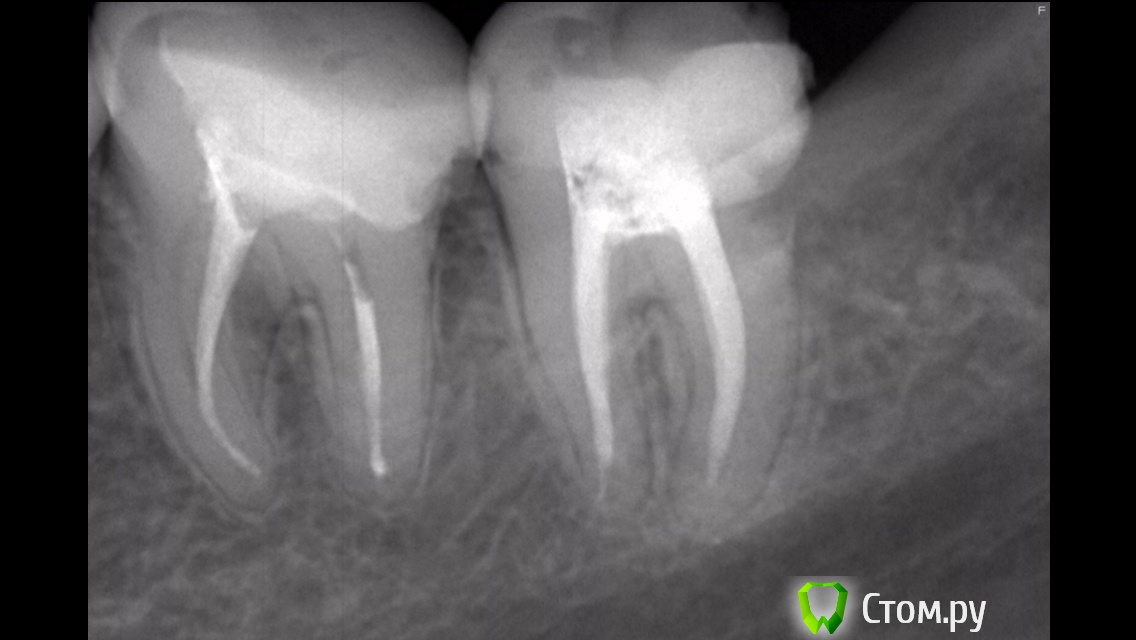

misskate Опубликовано 11 октября, 2014 Автор Поделиться Опубликовано 11 октября, 2014 Добрый день! У меня вопрос по поводу правого зуба на снимке, у него отвалилась стенка, сегодня стоматолог на консультации мне сказала что зуб нужно удалять тк началось гниение корня. Так ли это? Какое мнение будет у экспертов. Спасибо. Ссылка на комментарий

red_butler Опубликовано 11 октября, 2014 Поделиться Опубликовано 11 октября, 2014 Так ли это? похоже что удалять, но точно можно сказать на очном осмотре 2 Ссылка на комментарий

IvanK Опубликовано 11 октября, 2014 Поделиться Опубликовано 11 октября, 2014 похоже что удалять, но точно можно сказать на очном осмотре +1 Ссылка на комментарий